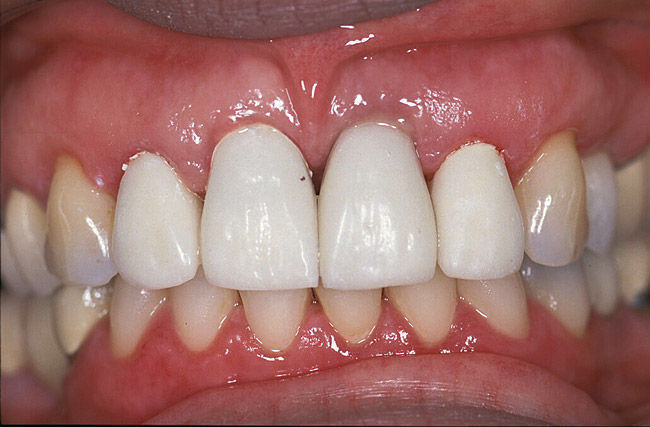

Fig 12. Provisionalization allows complete development of the soft tissue, evaluation of the incisal length, and final patient approval before moving to a final restoration.

Figure 12

Fig 13. A correctly developed provisional on an implant will demonstrate a reduced subgingival contour unless there is a desire to push the tissue more apically.

Figure 13